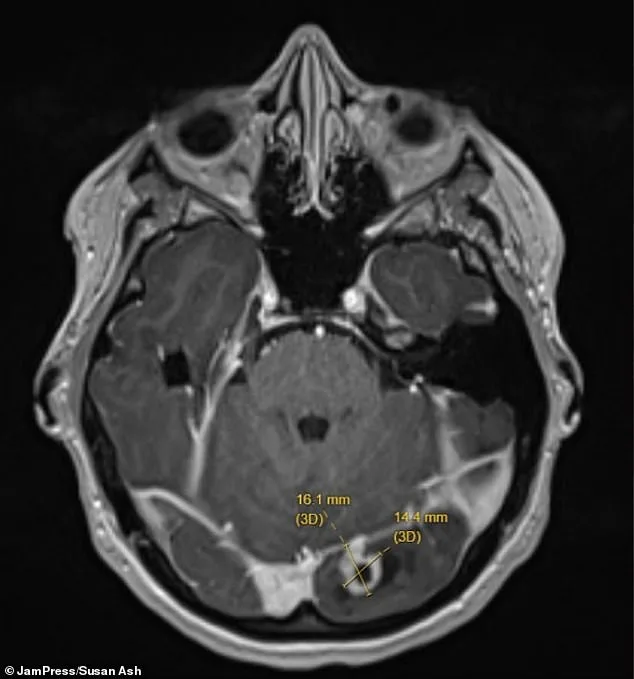

The above is a picture of the scan of Ms Ash' brain, with the tumor shown by the yellow lines.

But when I went back to work seven weeks postpartum, the duration and frequency of these episodes [headaches and blurred vision] was increasing.' Doctors found the tumor on her left occipital lobe — the part of the brain at the back of the head responsible for processing visual information from the right eye.

She was rushed to hospital, where imaging scans revealed a marble-sized tumor pressing on her brain.